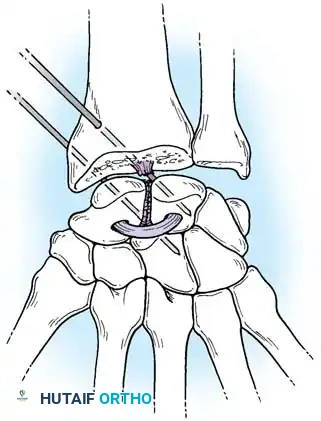

Fig. 66-76 Radioscaphoid ligament (RSL) and surrounding capsular anatomy.

Closed reduction with percutaneous pinning (placing 0.045-inch K-wires from the scaphoid to the capitate and lunate) can be attempted. However, open reduction through a dorsal approach is generally preferred. This allows direct closure of the scapholunate gap, K-wire fixation, and primary repair of the dorsal SL interosseous ligament using suture anchors.